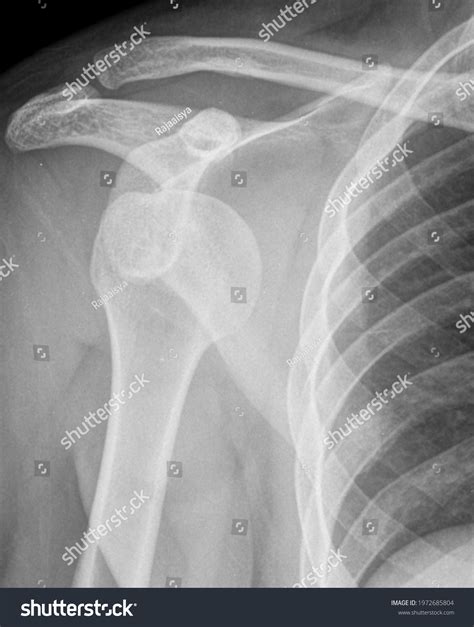

Diagnostic Procedures and Imaging

Before any treatment is attempted, a healthcare provider must assess the stability and neurovascular status of the limb. Diagnostic imaging is critical to rule out fractures—particularly Bankart lesions or Hill-Sachs deformities, which are common complications. The following table highlights common clinical findings associated with the injury:

Diagnostic Method Purpose

X-ray (AP and Scapular Y views) Confirms the direction of dislocation and excludes fractures.

Physical Exam Assesses neurovascular health (checking radial pulse and sensation).

MRI Evaluates soft tissue, specifically the labrum and rotator cuff.

The immediate goal is reduction—the process of guiding the humeral head back into the glenoid socket. This procedure is performed by medical professionals using various techniques, including the Stimson technique, traction-countertraction, or external rotation methods. Once the shoulder is reduced, the primary focus shifts to immobilization and protection.